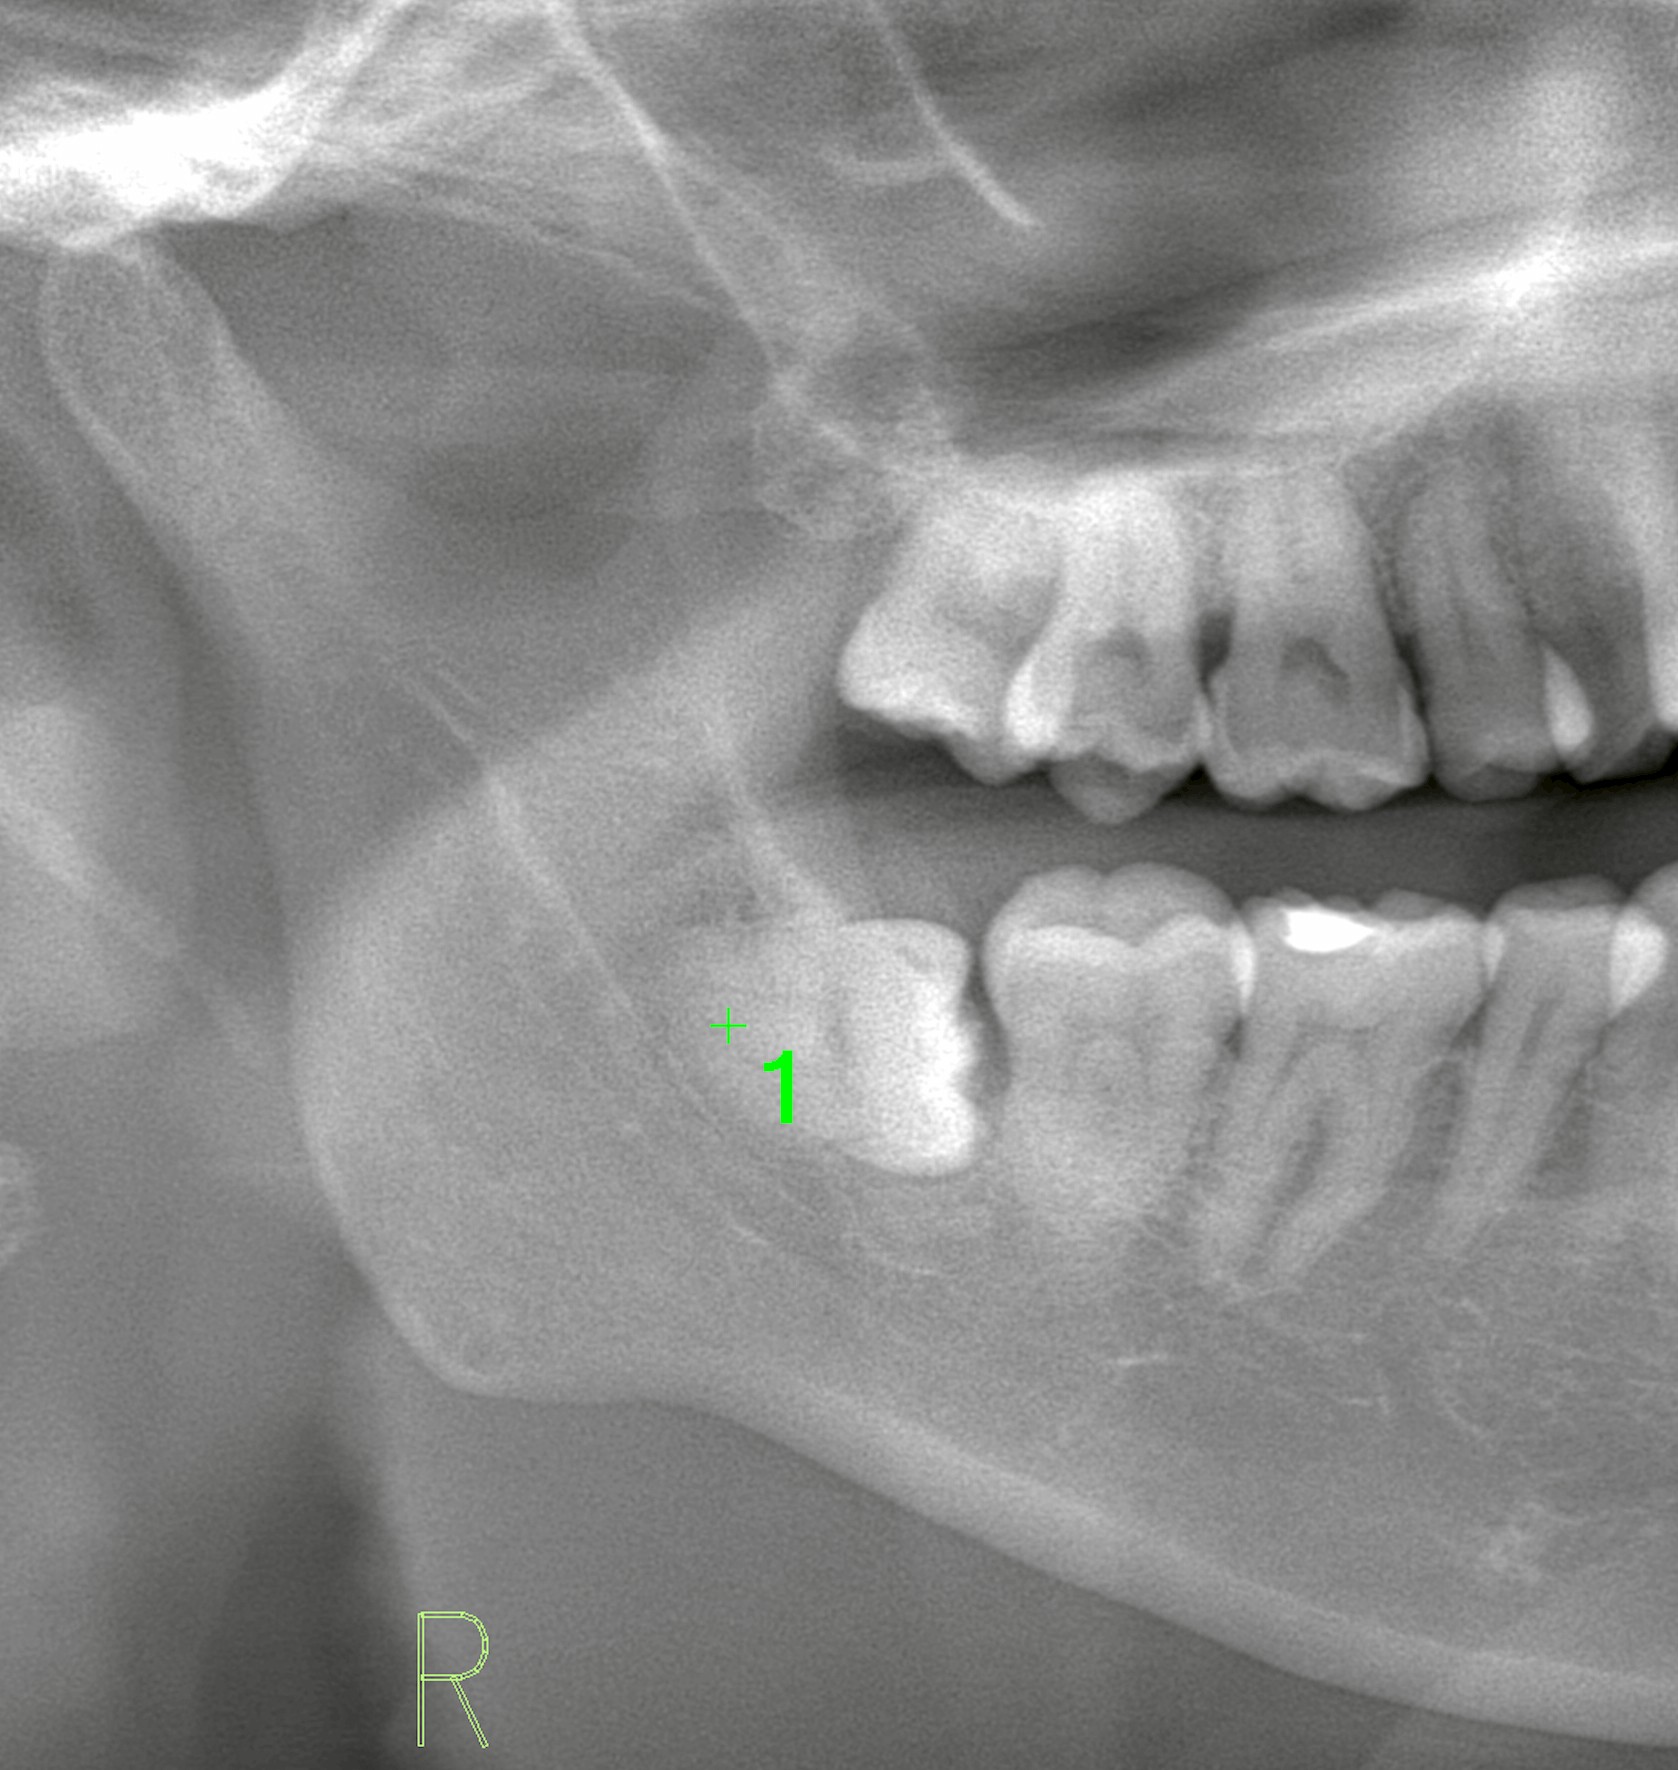

右下の親知らずが水平に埋まっており、定期的に腫れを繰り返すとのことで抜歯を希望されました。

当院にてCT撮影を行ったところ、確かに下歯槽神経に近接していましたが、直接の接触は認められませんでした。

このように、パノラマX線だけでは判断が難しいケースでも、CTによって三次元的に確認することでリスクを正確に分析できます。